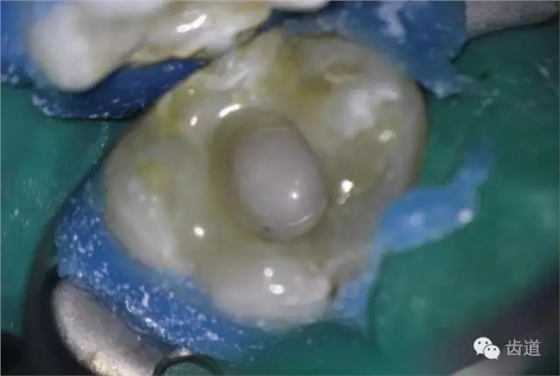

10. 術(shù)后即刻口內(nèi)照片

檢查:術(shù)后半年回訪,37牙體及合面嵌體未見(jiàn)缺損及裂紋,邊緣密合,未探及繼發(fā)齲,探痛-,叩痛-,松動(dòng)-,冷水刺激痛-,未探及牙周袋及附著喪失,牙齦無(wú)紅腫,X線片檢查示根尖周膜連續(xù)性恢復(fù),根尖周透射影消失。

1. 術(shù)后半年口內(nèi)照片